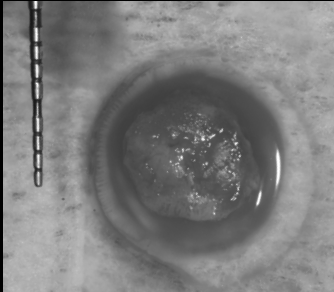

上唇の腫脹を認め、CT検査にて根尖部に嚢胞様透過像を認めた。左上の前歯が不自然に大きく噛み合わせが強くなっていたことがフレアアップの一因と考える。精密根管治療を行い、感染経路を遮断したのち歯根端切除術にて嚢胞を摘出した。

治療中